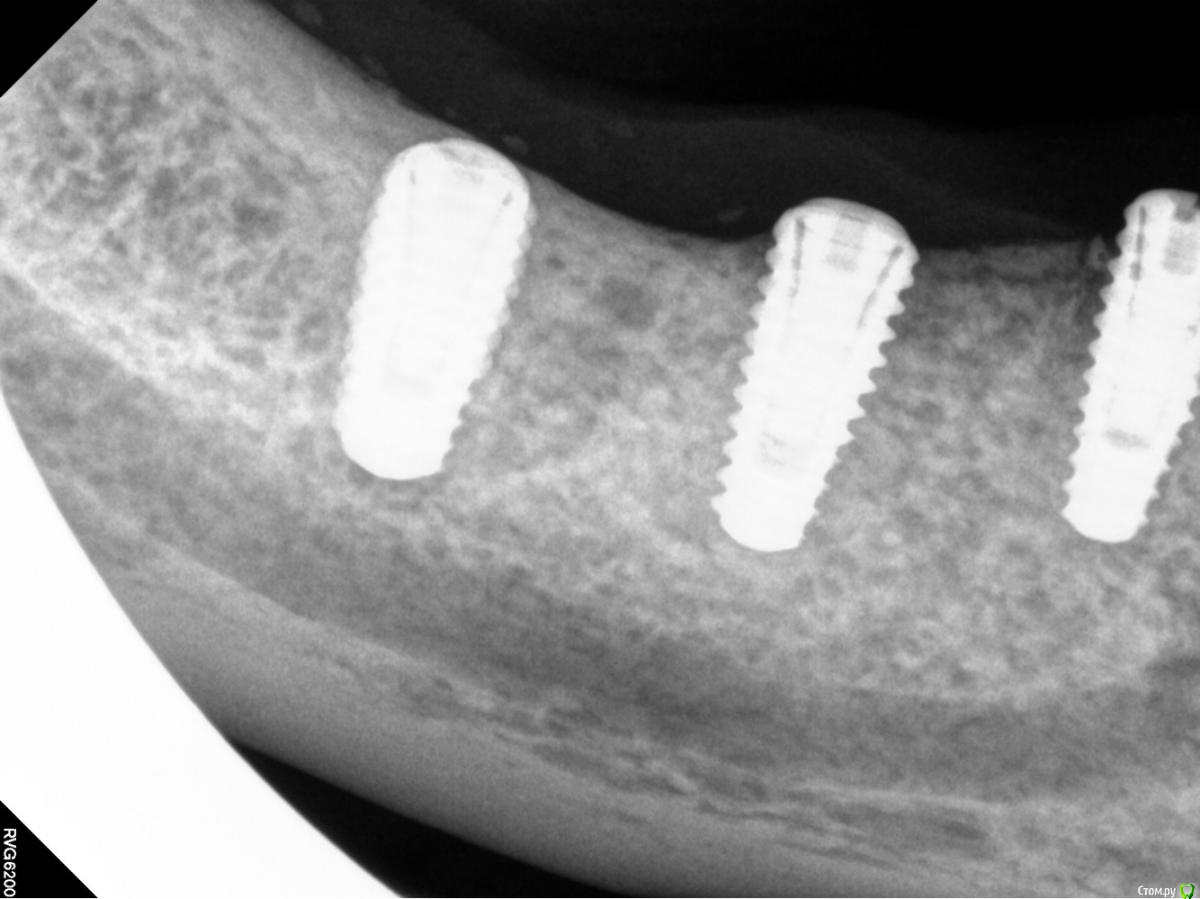

Orange1 Опубликовано 14 февраля, 2017 Поделиться Опубликовано 14 февраля, 2017 Здравствуйте коллеги.Проведена имплантация Megagen лето 2016.Ваше мнение по поводу обнажения витков.Помогите советом. Как С ними справиться.Спасибо! Ссылка на комментарий

Orange1 Опубликовано 14 февраля, 2017 Автор Поделиться Опубликовано 14 февраля, 2017 Вот такая проблема Ссылка на комментарий

Orange1 Опубликовано 15 февраля, 2017 Автор Поделиться Опубликовано 15 февраля, 2017 Согласен, если справится с ними, то шашлычек может помочь. Когда ставили, заглубили на какой уровень?Погружал на 0.5 Ссылка на комментарий

dok1 Опубликовано 15 февраля, 2017 Поделиться Опубликовано 15 февраля, 2017 Без обид. Сомнительно, что погружали. По логике погружение - это со стороны самой глубокой "стороны". Но тут проблем действительно не наблюдается особых. За шашлык + 1000. Что за система,если не секрет? Сомневаюсь в догадках. 1 Ссылка на комментарий

DrNice Опубликовано 15 февраля, 2017 Поделиться Опубликовано 15 февраля, 2017 Без обид. Сомнительно, что погружали. По логике погружение - это со стороны самой глубокой "стороны". Но тут проблем действительно не наблюдается особых. За шашлык + 1000. Что за система,если не секрет? Сомневаюсь в догадках. Здравствуйте коллеги.Проведена имплантация Megagen лето 2016.Ваше мнение по поводу обнажения витков.Помогите советом. Как С ними справиться.Спасибо! Да я тоже сомневаюсь в полном погружении, хотя они по протоколу должны погружаться. Ссылка на комментарий

Orange1 Опубликовано 17 февраля, 2017 Автор Поделиться Опубликовано 17 февраля, 2017 Да я тоже сомневаюсь в полном погружении, хотя они по протоколу должны погружаться.Погружал.думаю сверхкомпрессия съела.сейчас бы делал с времянками.Вчера раскрылся.удалил 18.шашлычок на 4.5.наблюдаю жду результата.фото к сожалению не делал.спасибо за советы коллеги. Ссылка на комментарий

Orange1 Опубликовано 17 февраля, 2017 Автор Поделиться Опубликовано 17 февраля, 2017 Кстати витки просвечиваются и более апикально.торк выдерживает.как с ними в будущем кто то наблюдал? Ссылка на комментарий